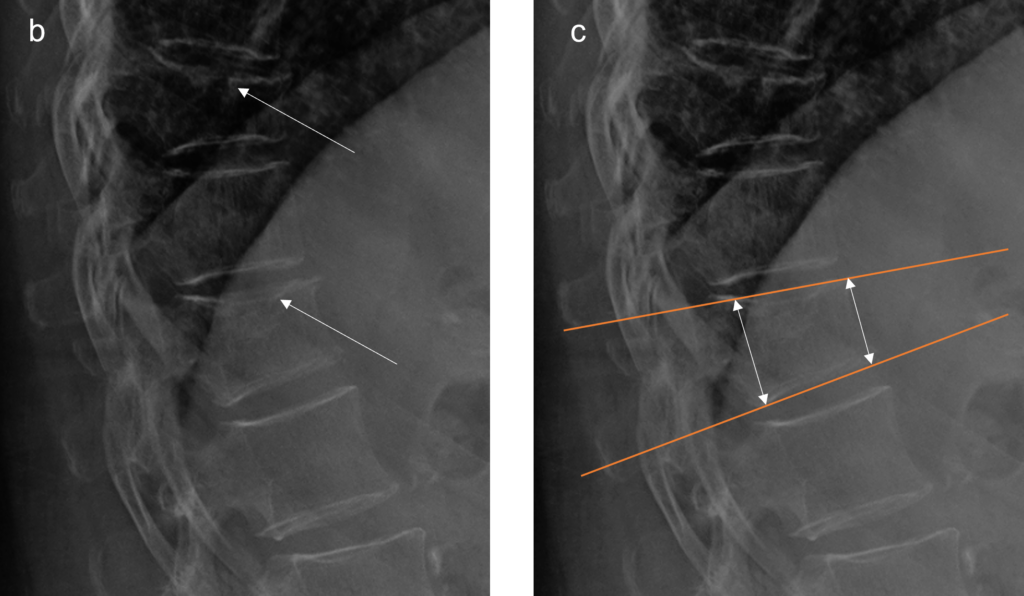

Il radiologo o l’operatore specializzato esamina le vertebre da T4 a L4 e assegna a ciascuna un punteggio di gravità basato sulla riduzione percentuale dell’altezza vertebrale rispetto all’altezza di riferimento (solitamente l’altezza posteriore della stessa vertebra o l’altezza di una vertebra adiacente sana).

La misurazione quantitativa computerizzata automatizza questo processo posizionando sei punti (reperi) su ogni corpo vertebrale, calcolando istantaneamente i rapporti tra le altezze anteriore, centrale e posteriore.

Uno degli aspetti più complessi della morfometria è la diagnosi differenziale. Non tutte le vertebre che presentano una riduzione dell’altezza sono fratture da fragilità. Una corretta interpretazione richiede la distinzione tra “frattura” e “deformità non fratturativa“.10

Mentre il metodo di Genant si focalizza sulla perdita di altezza, l’ABQ mette al centro l’integrità della piastra terminale. Se la piastra terminale è integra e non mostra depressioni centrali o interruzioni, la deformità è più probabilmente riconducibile ad una variante anatomica o a rimodellamento degenerativo piuttosto che a una frattura da fragilità.

L’integrazione di entrambi i metodi aumenta drasticamente la specificità diagnostica.